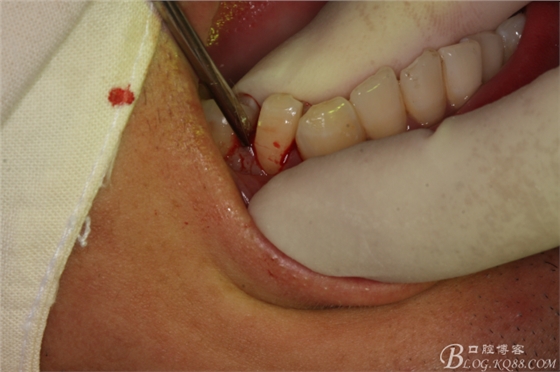

圖20.金剛砂車(chē)針片切44牙冠、消除鄰牙阻力

圖21.片切完成的44牙冠

圖22.微創(chuàng)挺增間隙

圖23.放置牙鉗拔除